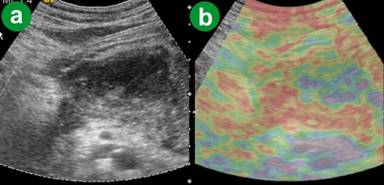

The ARFI-VTQ values for the pancreatic parenchyma ranged from 0.80 m/s to 2.21 m/s with a mean value of 1.276±0.293 m/s (Table 2, Figure 1). On eSie touch elastogram, normal pancreatic parenchyma and peripheral fat appeared white to light gray (scores 1-2) on gray scale while on the color scale, it was green/purple to yellowish green (scores 1-2), thus indicating softness of the normal tissue (Figure 2).

Figure 2. Normal pancreas. a. US B-mode image. b. eSie touch color scale image (green/purple to yellowish green: score 1-2). c. eSie touch gray scale image (white to light gray: score 1-2). |

The ARFI-VTQ values for the pancreatic parenchyma ranged from 0.65 m/s to 1.74 m/s with a mean value of 1.240±0.235 m/s (Table 2; Figure 1). On eSie touch elastogram the pancreatic parenchyma and peripheral fat appeared light gray to gray (scores 2-3) on gray scale (Figure 3), while on the color scale it was yellowish green to yellow (scores 2-3; Figure 4).

Figure 3. Chronic pancreatitis. a. US B-mode image. b. eSie touch gray scale image (light gray to gray: score 2-3). |

Figure 4. Chronic pancreatitis. a. US B-mode image. b. eSie touch color scale image (yellowish green to yellow: score 2-3). |